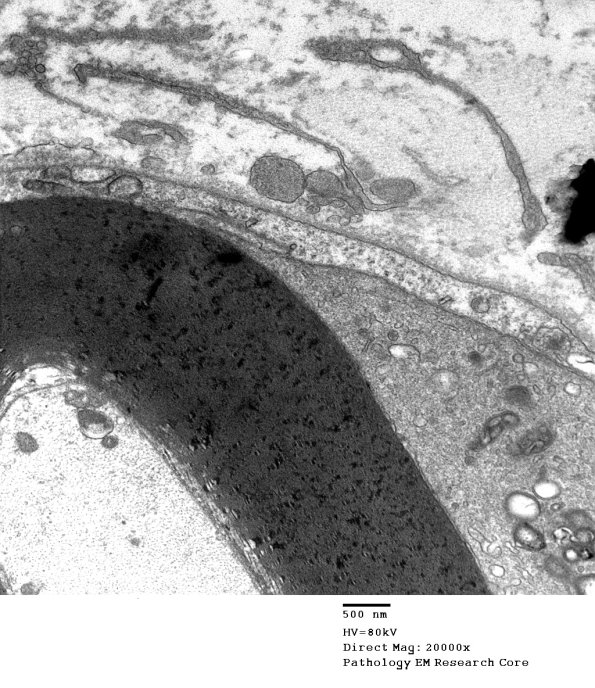

An early lesion where there is little myelin loss and only myelin debris in the macrophage. However, the tongues of macrophages are easy to recognize against the background of Schwann cell cytoplasm and small processes. (electron micrographs)